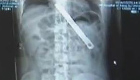

4年前,北京阜外醫(yī)院救治了一名患有先天性心臟病的嬰兒。手術成功了但孩子聲門狹窄,父母說是醫(yī)院造成的,于是把孩子留在醫(yī)院就沒再回來。日前,此案被強制執(zhí)行,孩子見到媽媽第一句話竟是:“阿姨好”。